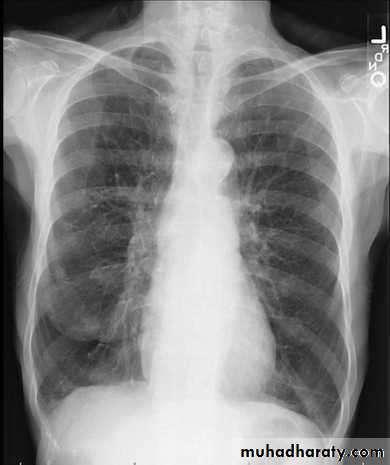

Left lower lobe collapse has distinctive features, and can be readily identified on frontal chest radiographs, provided attention is paid to the normal cardiomediastinal contours. The shadow cast by the heart does however make it harder to see than the right lower lobe collapse

Radiographic features

Left lower lobe collapseis readily identified in a well penetrated film of a patient with normal sized heart, but can be challenging in the typical patient with collapse, namely unwell patients, with portable (AP) often under-penetrated films, often with concomitant cardiomegaly. Features to be observed include :

triangular opacity in the posteromedial aspect of the left lung

edge of collapsed lung may create a 'double cardiac contour'

left hilum will be depressed

loss of the normal left hemidaphgragmatic outline

loss of the outline of the descending aorta

Non-specific signs indicating left sided atelectasis are usually also be present including:

elevation of the hemidiaphragm

crowding of the left sided ribs

shift of the mediastinum to the left

On lateral projection the left hemidiaphragmatic outline is lost posteriorly and the lower thoracic vertebrae appear denser than normal (they are usually more radiolucent than the upper vertebrae) .